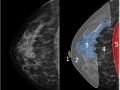

Tag: mastologia

Bases físicas da mamografia